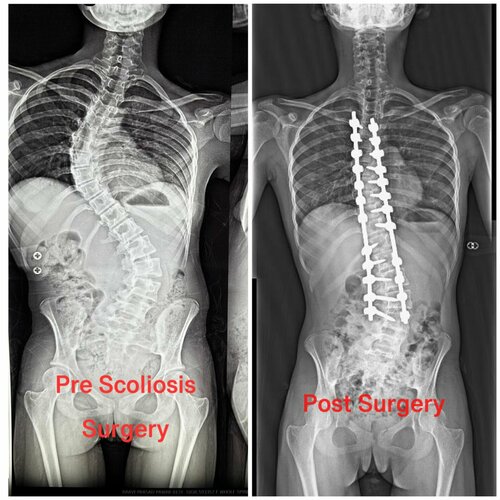

Successful Scoliosis Treatment by Dr. Ajay Kothari at Sancheti Hospital

Dr. Ajay Kothari, Consultant Spine, Scoliosis, and Endoscopic Spine Surgeon at Sancheti Hospital, Pune, successfully treated a 12-year-old girl with a severe and progressively worsening scoliosis deformity. Dr. Kothari performed a challenging yet advantageous surgery using advanced technology such as the O-arm, navigation, and neuro-monitoring piezoelectric knife. The patient completely recovered, with her deformity nearly corrected to normalcy, and was discharged on the fifth day. Within a month, she was able to rejoin her school program. Dr. Kothari emphasizes that, with special expertise and high-end technology, scoliosis treatment can be life-changing for young patients and is now affordable without compromising quality. Scoliosis  Treatment is challenging but possible Needs special expertise  Needs Hi- End technology  Proper treatment- Very rewarding Life-changing for the small kids  In Today’s era affordable treatment is possible without compromising on quality   Read More - Dr. Ajay Kothari was awarded DNB Orthopedics gold medalAvoid Supermarket Syndrome: Tips from Dr. Ajay Kothari on Preventing Spine and Joint Injuries